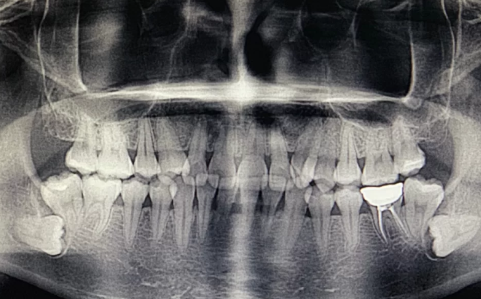

牙医建议拔掉智齿主要是因为牙齿反复发炎,会影响邻近的牙齿。

1、反复炎症:智齿出牙不完整,龈冠覆盖后侧部分形成冠周袋。不注意个人卫生,局部软组织往往会发炎,出现疼痛症状,所以需要拔掉智齿才能有效改善。

2、影响邻近牙齿:如果牙齿生长位置不正确而拥挤,就有可能对邻近牙齿造成损害,使咀嚼功能严重受损,因此需要拔除智齿。